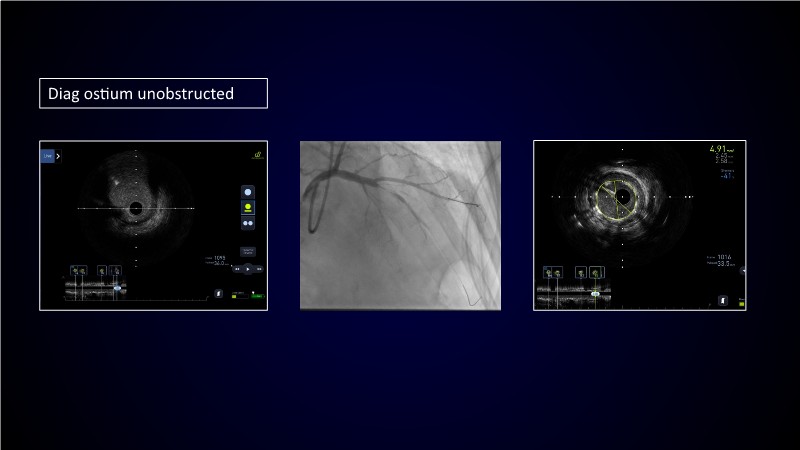

Calcified coronary lesions are a major challenge in PCI. This PCRGulf-GIM 2025 session showcases a complex case with intravascular imaging, highlighting how IVUS 123 guides each step.

From planning the procedure and understanding calcium distribution, to lesion preparation with modern modification tools, and post-PCI assessment to confirm stent expansion and detect complications, this session demonstrates practical, imaging-driven strategies.

Learn how careful preparation and modern techniques improve outcomes in treating severe calcium, calcified nodules, and in-stent restenosis.